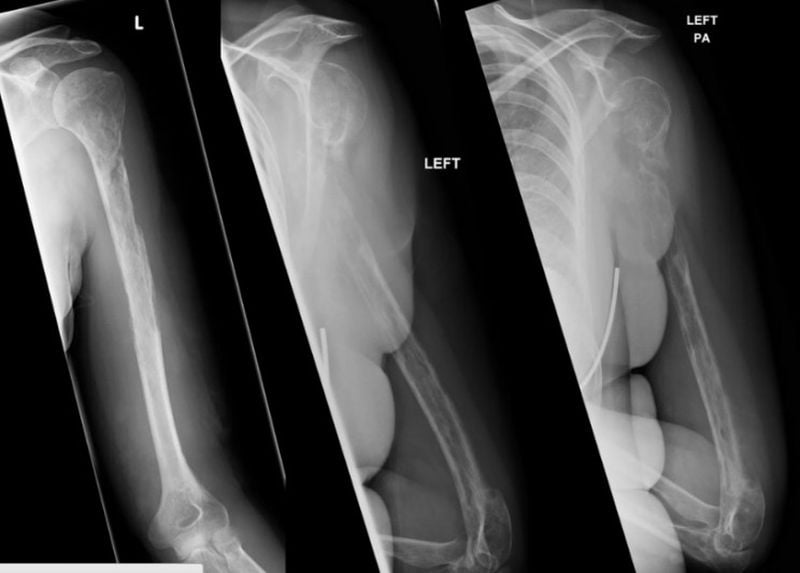

Um raio-X inicialmente revelou uma lesão em seu úmero, sugerindo que ela pode ter câncer, entretanto seus resultados de biópsia foram inconclusivos.

O mais alarmante de tudo foi o fato de que, em cada raio-X sucessivo, os ossos de seus braços pareciam estar gradualmente desaparecendo.

Ela acabou sendo diagnosticada com doença de Gorham-Stout ou “desaparecimento dos ossos” – uma condição extremamente rara que permanece um enigma médico.